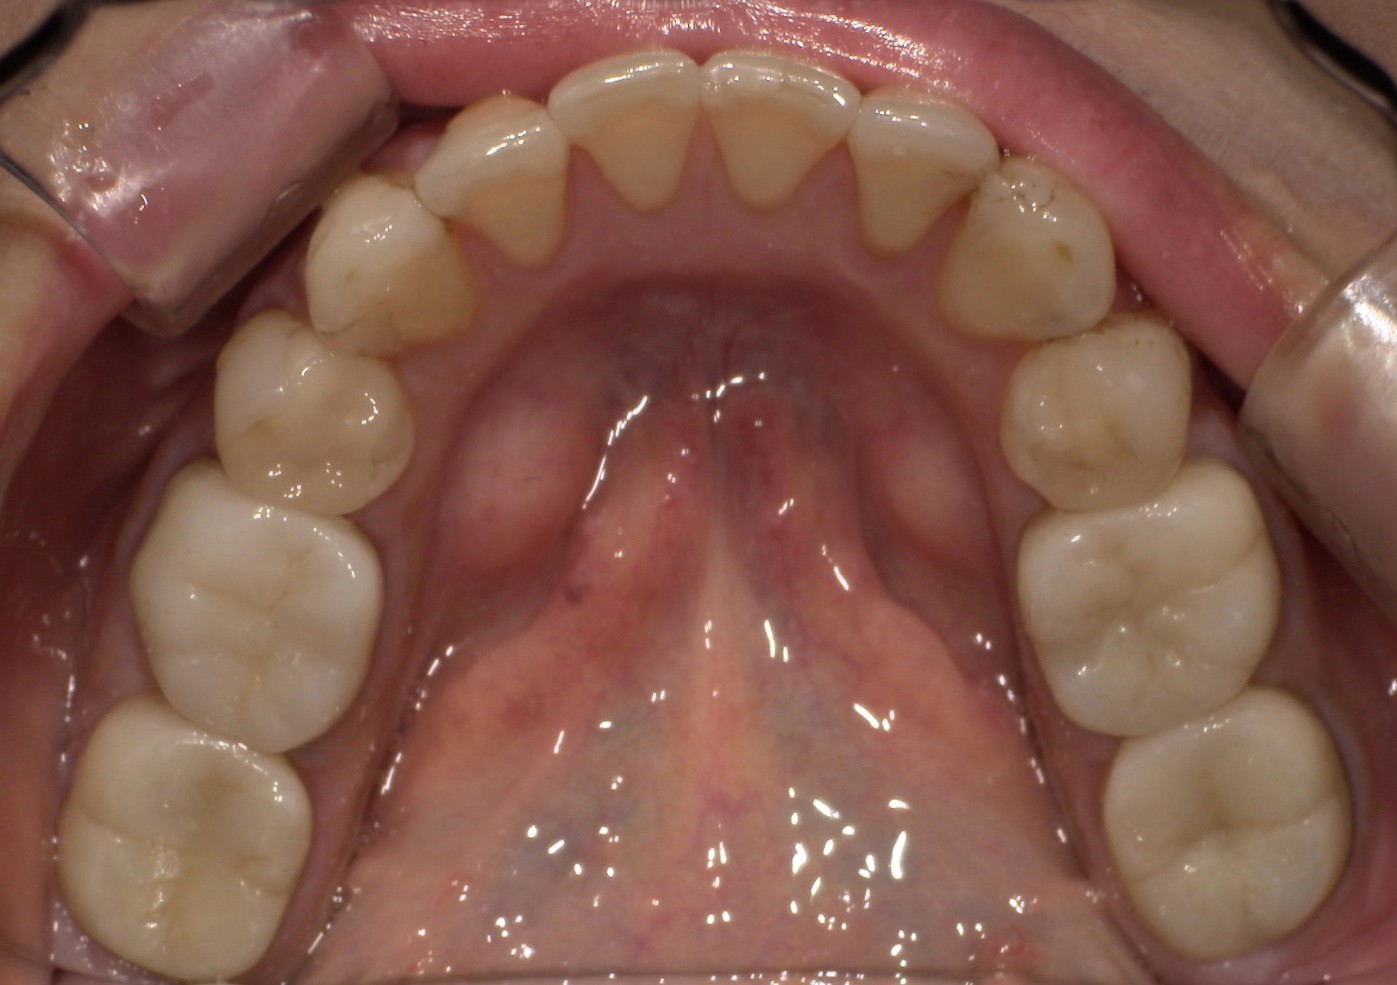

CASE 03

Before

After

施術内容左右下顎の第一・第二大臼歯の銀歯(被せ物)をジルコニアクラウンに交換。右下第二小臼歯の銀歯(詰め物)をジルコニアインレーに交換。

治療期間3か月

リスク・副作用ジルコニアは非常に強度が高いですが、強い衝撃や極端に強い噛み合わせ、歯ぎしり・食いしばりなどがある場合、まれに割れたり欠けたりする可能性があります。

費用 454,400円

※表示金額は全て税込みです。